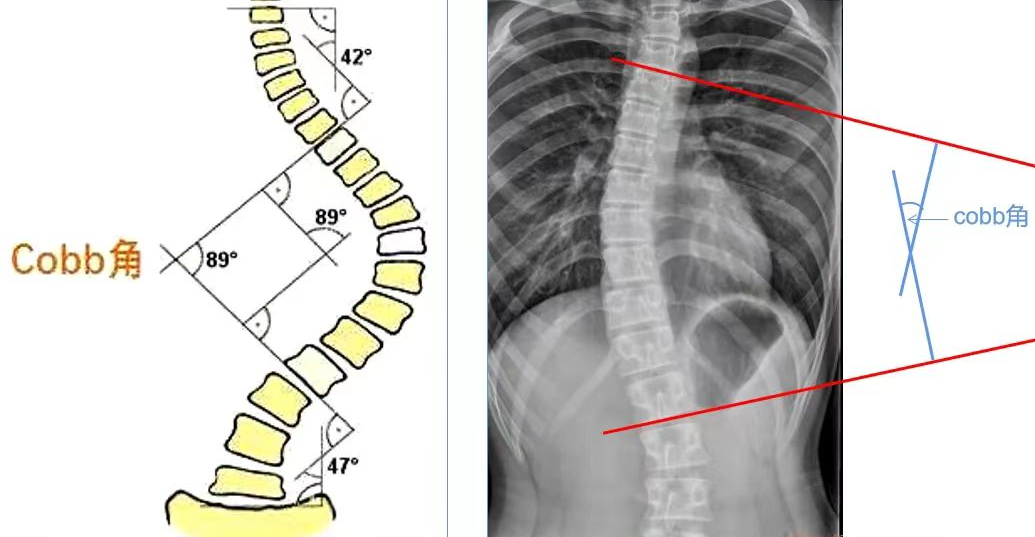

Cobb角是评估脊柱侧弯严重程度的一个重要指标,角度越大,代表侧弯越严重,治疗难度也会随之增加。国际脊柱侧弯研究会规定,站立位时Cobb角大于10°称为脊柱侧弯。

Cobb角测量方法:

先确定侧弯的上下端椎,就是侧弯中倾斜角度最大的椎体,在上端椎的上缘和下端椎的下缘各划一条横线,两条横线的各做一条垂线,这两条垂线的夹角就是Cobb角。